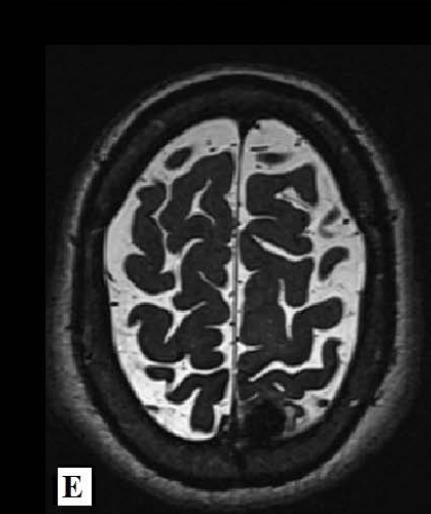

We report a rare case of Wilson’s Disease with neurologic features in a 31-year-old man. This disease consists of a disturbance of copper metabolism secondary to a mutation in the gene responsible for encoding the tissue transporter and the enzyme that incorporates the excess element into bile, generating toxic accumulation in the liver, cornea, and central nervous system. According to his wife, the patient had been treated for an unspecified mood disorder. The clinical picture was characterized by depressive mood, anhedonia, and anxiety. He had his first seizure episode on December 3rd, 2021. He progressed with dysarthria, ataxic gait, dystonia of the right-hand flexor muscles, and intermittent urinary incontinence. Marked worsening was observed after the diagnosis of COVID-19 in February 2022. At the clinical evaluation on March 24th, risorius muscle dystonia (risus sardonicus), resting tremor, and Kayser Fleischer rings at slit-lamp examination was also noted.

Detailed image from a research journal sample.